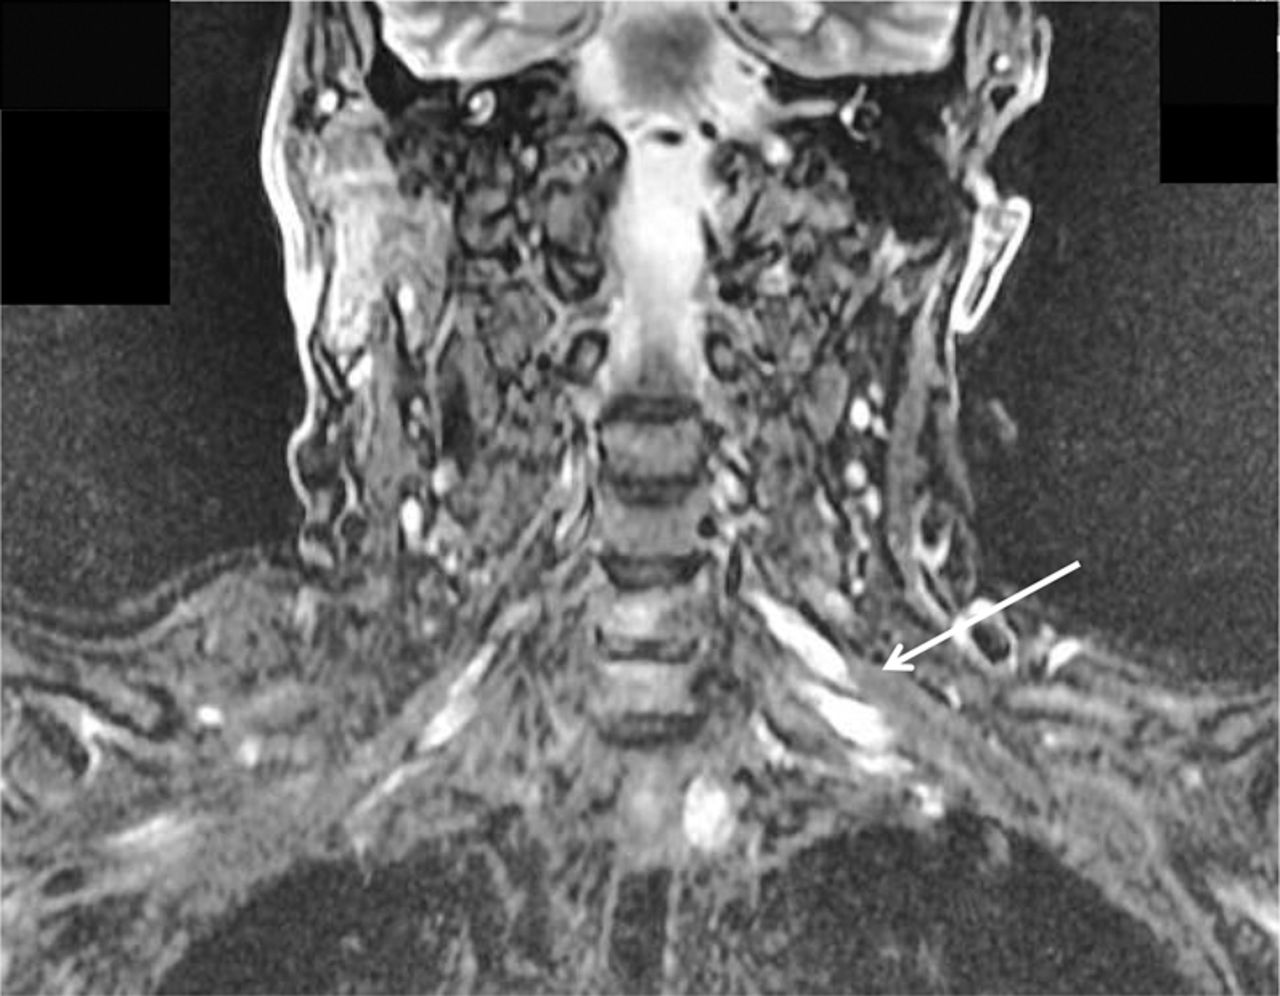

一位68岁的男子抱怨多年来左臂不协调、虚弱。临床检查显示假性震颤和轻微的左臂整体无力,袜子模式振动和针刺不敏感,只有轻微的左手本体感觉障碍首页®网址:首页Neurology.org).神经传导研究显示感觉电位普遍缺失或严重减弱,上肢多处运动传导阻滞(图1).MRI显示左臂丛神经根及干不对称扩大(图2).慢性炎性脱髓鞘性多神经根神经病可引起震颤,1但多灶性获得性脱髓鞘感觉和运动神经病,2不对称形式,尚未报道引起假手足徐动症。